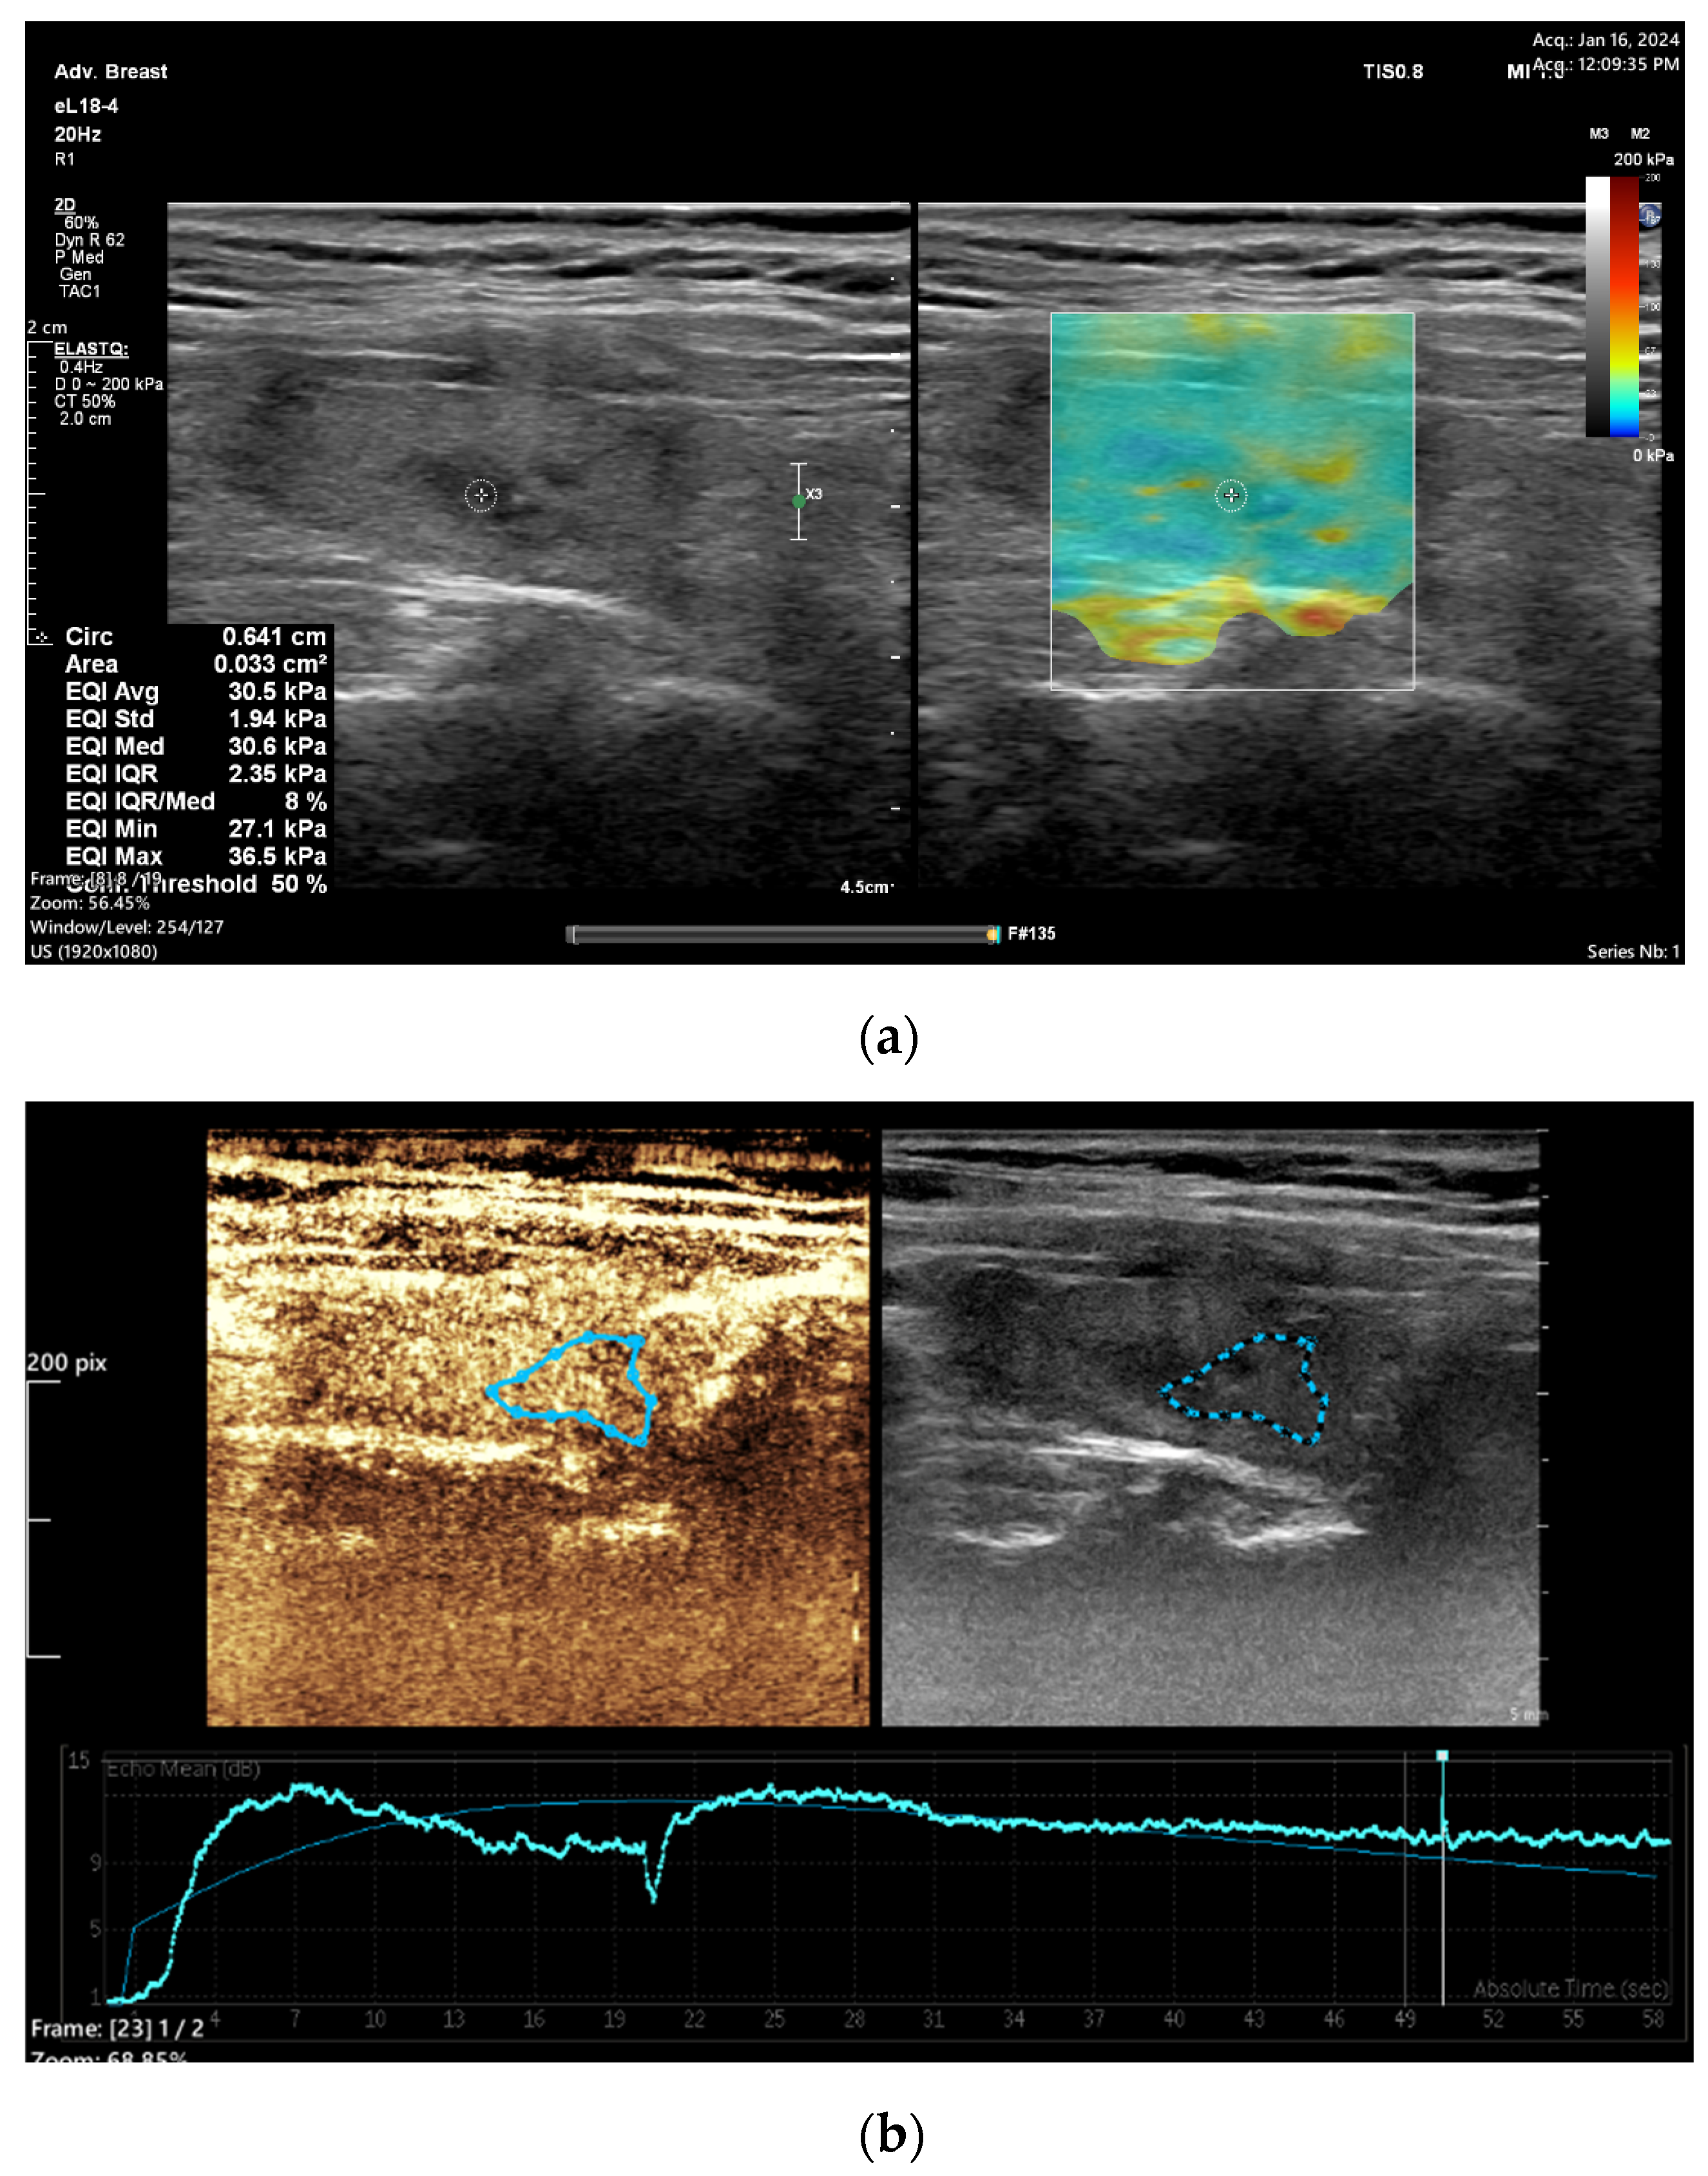

3.1. Elastography

3.2. CEUS